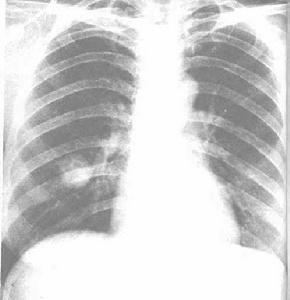

肺炎性假瘤臨床上肺炎性假瘤並不常見,男女均可發生,患者年齡從1~70歲,但年輕人多見,大多在30歲左右。今一半的病人無症狀,其餘可有肺及胸部的有關症狀,如咳嗽、咯血、呼吸短促及胸痛。有的可有發熱。病變可發生於任何肺葉,X線常表現為孤立的、界限清楚的圓形或卵圓形包塊。較大者腫塊界限不清,偶見鈣化或空洞形成。

肺炎性假瘤的診斷存在一定的困難,患者的臨床症狀較難與慢性支氣管炎及肺部惡性腫瘤鑑別。胸部X線檢查為圓形或橢圓形,邊緣光滑銳利的結節影,有些邊緣模糊,似有毛刺或呈分葉狀,與肺癌很難鑑別。肺炎性假瘤在肺部無明確的好發部位,大小可以從1cm到16cm,多數在4cm以下。這些都給診斷造成困難。

胸部X線片及CT掃描,有直徑1~6cm圓或橢圓形孤立塊影,中等密度,質地均勻,邊緣不甚清楚,少數可有胸膜粘連影,多數在肺的外周.診斷有困難或不能除外惡性者,應行開胸或經胸壁肺活檢。

肺炎性假瘤X線表現:假瘤可發生在肺的任何部位,球型瘤體由於有較完整的假性包膜,因此輪廓清楚,邊緣光滑,周圍肺野清晰。團塊狀的瘤體由於假包膜不完整,一般境界不清,邊緣模糊,部分病灶密度濃淡不勻,如多次並發急性炎症,可造成“瘤”影擴大,在其周圍恰似炎性浸潤的片狀影。崔氏報導的“桃尖征”本組出現率不高,其病理基礎可能是一種腫瘤包膜粘連的徵象;CT表觀:CT圖像把假瘤與肺的界面,特別是假瘤的邊緣、密度、空洞、長毛刺影與胸膜粘連等顯示得非常清楚。本文36例胸部平片僅2例見有空洞影,而25例CT掃描發現9例小空洞,這種空洞可以單發也可多發。少數瘤體切開時可見膿性物。假瘤邊緣可以不規則或呈鋸齒樣,也可呈分葉狀。CT肺窗圖像上,腫瘤邊緣可清楚地顯示炎性滲出影。長毛刺、與胸膜緊貼或有粘連帶等對本病的診斷具有一定的意義。假瘤術前診斷的主要方法靠X線、CT檢查。胸部正側位相能顯示假瘤的全貌,CT掃描有助於顯示瘤體內部結構(即空洞、鈣化、毛刺、血管、纖維索條影等)。